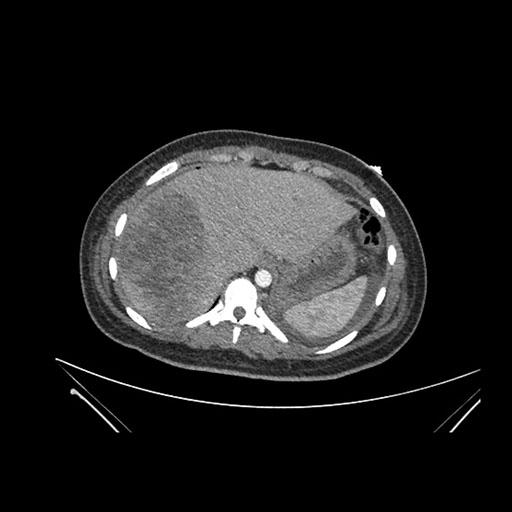

Axial Venous